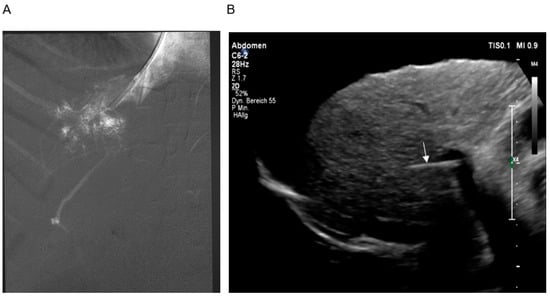

2.2. TIPS

2.2.2. Technique of TIPS Implantation

2.3. Pre- and Post-Interventional Management